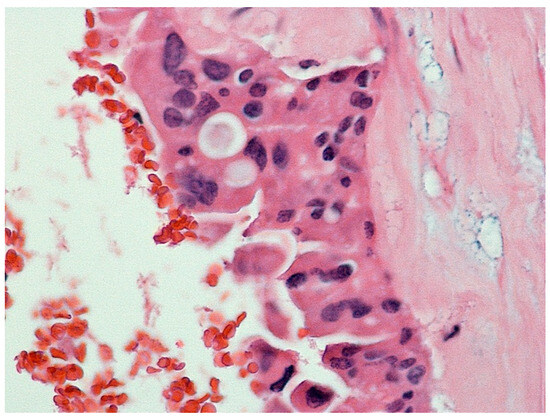

| Feature | Case 1 | Case 2 |

| Patient Demographics | 60-year-old Caucasian male | 28-year-old Caucasian female |

| Clinical Presentation | Incidental discovery of an 8 × 8 × 9 cm hepatic cyst | Presented with dyspnea, vomiting, jaundice, fever |

| Diagnostic Methods | MRI, MRCP, ERCP, histopathological examination | CT, MRI, laparoscopic liver biopsy, histopathological examination |

| Tumor Characteristics | Large cystic mass, thin walls, internal septa, papillary projections, enhancing solid components | Large lesion in left hepatic lobe, hyperintensity in T2-weighted images, restricted diffusion, contrast enhancement |

| Histopathological Findings | IPNB with foci of adenocarcinoma, oncocytic appearance, varying degrees of dysplasia, mucus within cyst | Adenocarcinoma with papillary clear cell and mucinous appearance, gland ectasis, cystic or pseudocystic aspects |